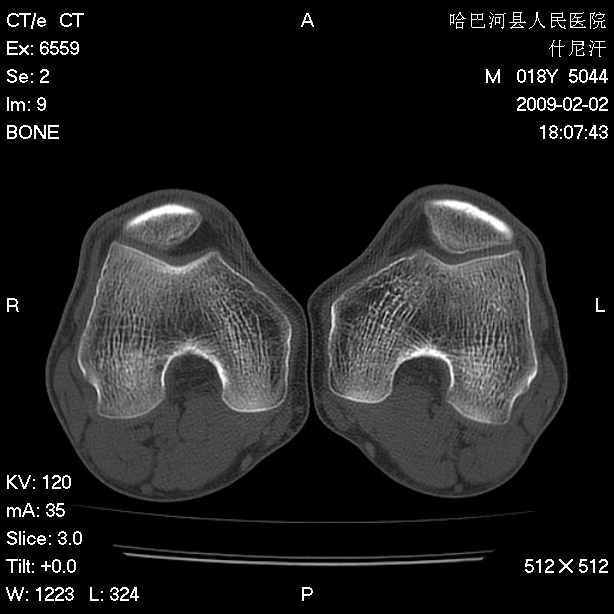

标题: CT17889:外伤后右膝关节反复疼痛3年余 [打印本页]

标题: CT17889:外伤后右膝关节反复疼痛3年余

ct未见明显异常。关节腔未见明显积液,半月板未见明显撕裂。但最好还是mri看看韧带及半月板情况。